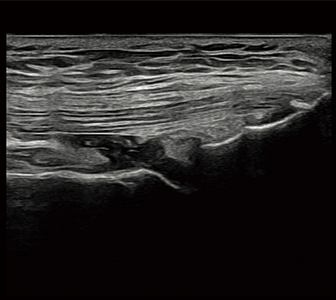

不明瞭部分をクリアに。

針先を見やすく。手技の精度と効率が向上。